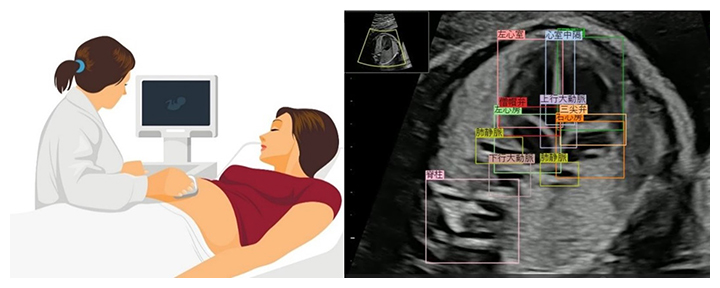

今回、共同研究グループが開発したAIシステムでは、胎児心臓超音波スクリーニング動画において確認すべき心臓血管構造の18部位を対象として物体検知技術[2]を適用し、正常構造として検出された部位を色付き枠で提示しました。次に、その部位検出情報を2次元データに変換し、縦軸に対象部位、横軸に検査時間経過を示し、各部位の検出結果を時系列で一覧表示するバーコードを生成しました。さらに、検査者が把握しやすいように心臓部[3]および流出路[3]を対象とした部位検出結果を検出率グラフで提示しました(図1)。正常胎児では、超音波プローブのスイープ走査に合致して、各診断部位を順番に検出できます。一方で、正常胎児が示すバーコードや検出率グラフから逸脱していた症例については、異常を疑う所見ありとして検査者に注意喚起を行います(異常検知[4])注6)。

図1 バーコードと検出率グラフ

左図:胎児心臓超音波スクリーニング動画上で検出された部位を色付き枠で囲む。右上図:縦軸に対象となる18部位、横軸に検査時間経過を示し、各部位の検出結果を時系列でバーコード表示。右下図:心臓部および流出路を対象とした部位検出結果を検出率グラフで示す。AIシステムのバーコードおよび検出率グラフにおいて、心臓部:9部位(心交差、心室中隔、右心房、三尖弁、右心室、左心房、僧帽弁、左心室、肺静脈)を赤色、流出路:4部位(上行大動脈、肺動脈、動脈管、上大静脈)を青色で示した。